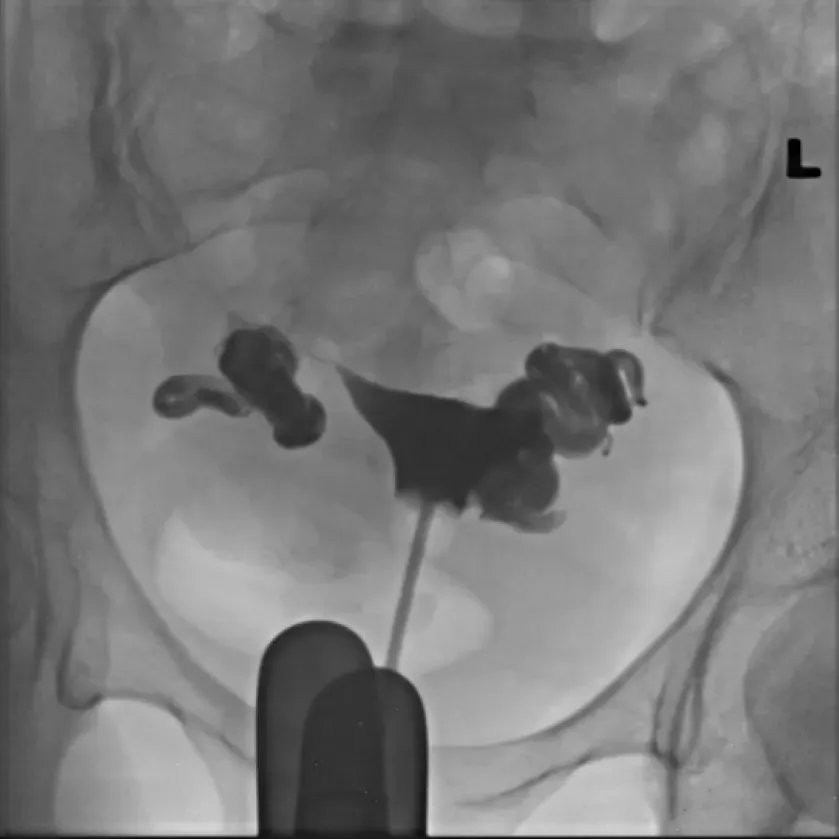

【115-1 醫學(六) 第73題】35 歲女性病人主訴不孕,子宮輸卵管攝影檢查發現如附圖。最可能之診斷為何?